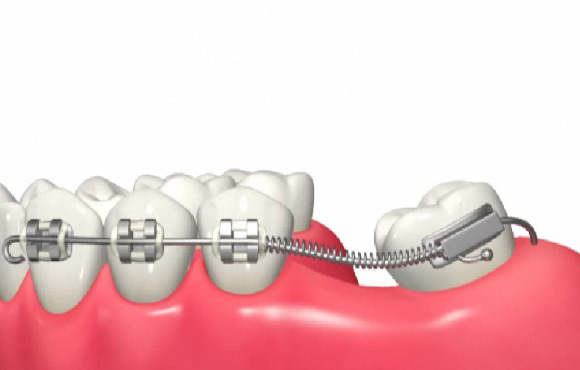

倒れている歯を起こす(アップライト)

手前の歯がなくなった後放置したことにより

奥の歯が手前に倒れこんできてこのままではブリッジやインプラント治療ができない。

バネの弾力により歯を起こしこの後インプラントやブリッジにより噛み合わせを回復することが可能になります。